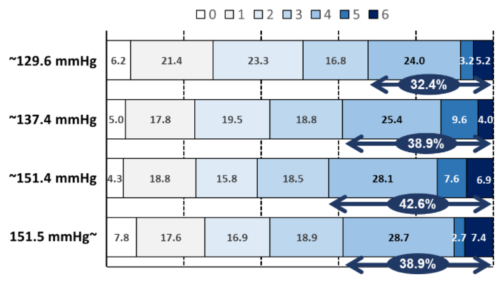

ニカルジピン静注による急性期脳出血患者の血圧管理: 研究参加者個々情報の統合解析

国循の研究チームが中核的に参加した前向き観察研究SAMURAI-ICHと第Ⅲ相無作為化比較試験ATACH-2は、いずれも...